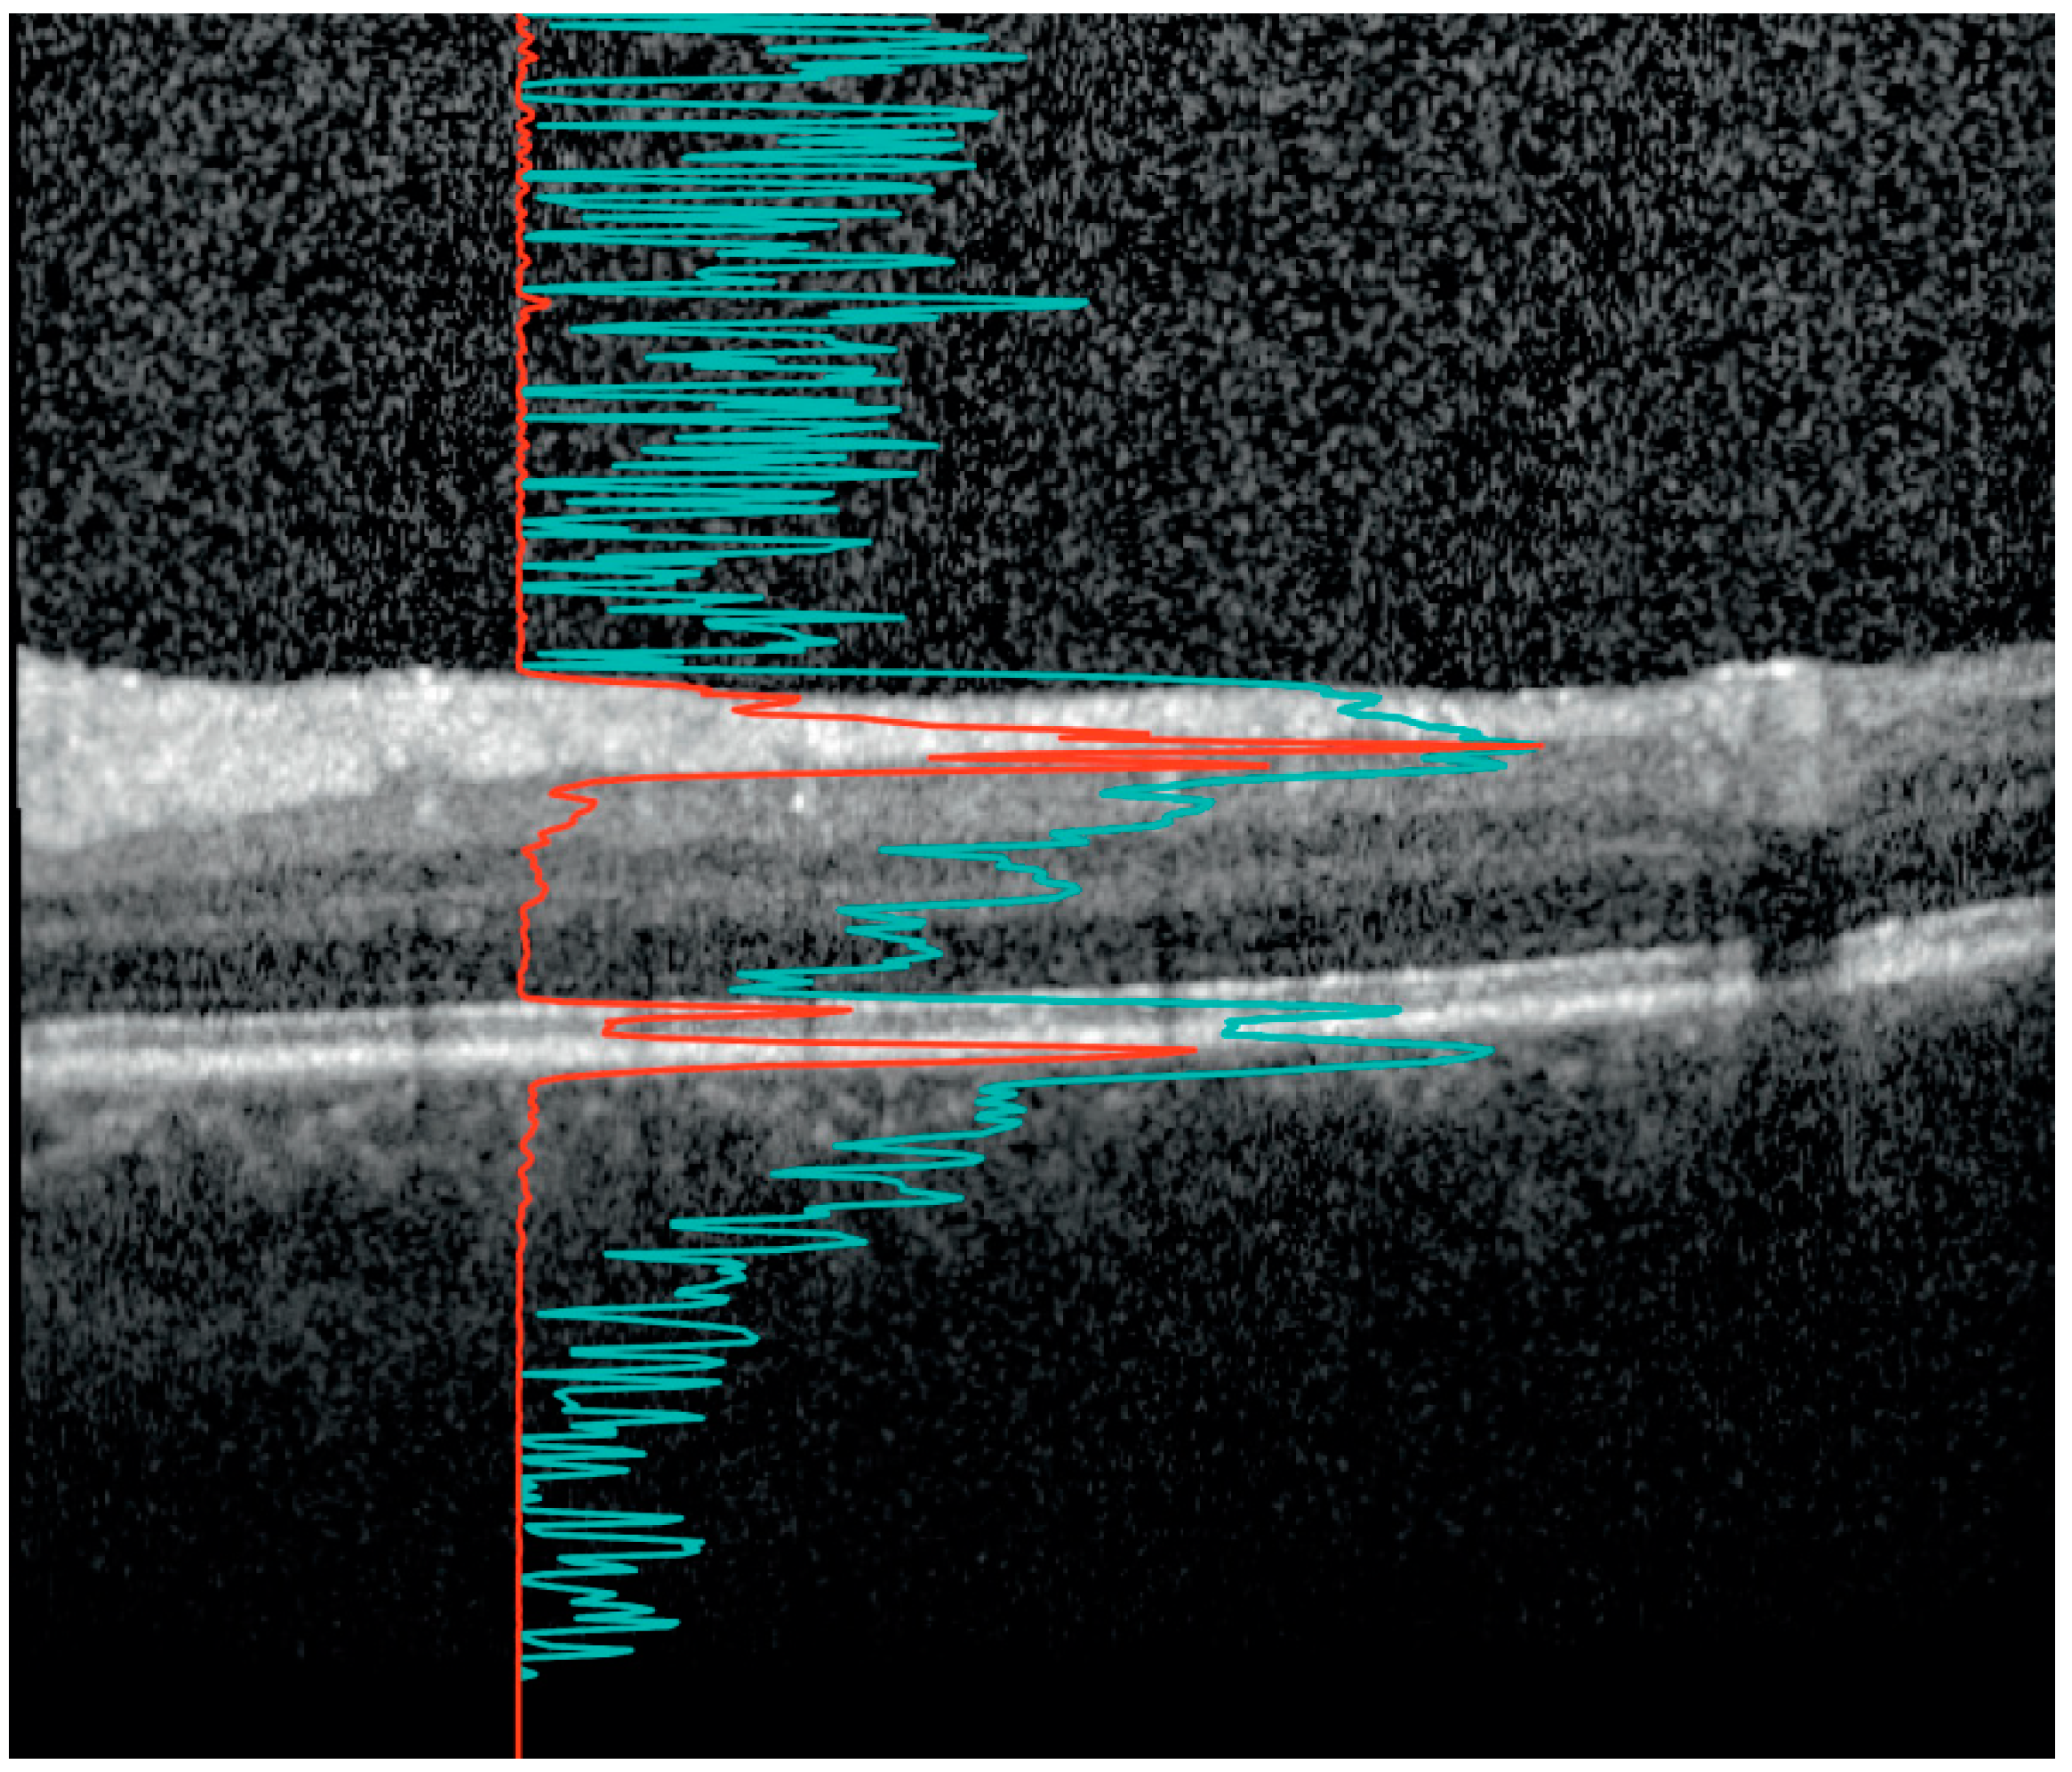

2.2. Retinal Layer Thickness and Vitreous Haze Measurements

- Montesano, G.; Way, C.M.; Ometto, G.; Ibrahim, H.; Jones, P.R.; Carmichael, R.; Liu, X.; Aslam, T.; Keane, P.A.; Crabb, D.P.; et al. Optimizing OCT acquisition parameters for assessments of vitreous haze for application in uveitis. Sci. Rep. 2018, 8, 1648. [Google Scholar] [CrossRef]

- Liu, X.; Kale, A.U.; Ometto, G.; Montesano, G.; Sitch, A.J.; Capewell, N.; Radovanovic, C.; Bucknall, N.; Beare, N.A.V.; Moore, D.J.; et al. OCT Assisted Quantification of Vitreous Inflammation in Uveitis. Transl. Vis. Sci. Technol. 2022, 11, 3. [Google Scholar] [CrossRef]

- Coric, D.; Ometto, G.; Montesano, G.; Keane, P.A.; Balk, L.J.; Uitdehaag, B.M.J.; Petzold, A.; Crabb, D.P.; Denniston, A.K. Objective quantification of vitreous haze on optical coherence tomography scans: No evidence for relationship between uveitis and inflammation in multiple sclerosis. Eur. J. Neurol. 2020, 27, 144-e3. [Google Scholar] [CrossRef] [PubMed]

- Keane, P.A.; Balaskas, K.; Sim, D.A.; Aman, K.; Denniston, A.K.; Aslam, T.; Equator Study Group. Automated Analysis of Vitreous Inflammation Using Spectral-Domain Optical Coherence Tomography. Transl. Vis. Sci. Technol. 2015, 4, 4. [Google Scholar] [CrossRef]